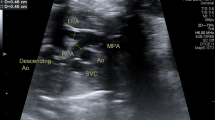

ABSTRACT: Maximum flow velocity waveforms were recorded in a longitudinal study from the fetal ascending aorta and fetal pulmonary artery in 46 normal pregnancies and, in addition, from the umbilical artery in 21 cases of intrauterine growth retardation between 19 and 33 wk gestation. In normal pregnancy, the mean peak systolic velocity (PSV) in the ascending aorta increased from 49.4 cm/s at 19 wk of gestation to 79.0 cm/s at 33 wk of gestation. The corresponding increase in PSV in the pulmonary artery was from 39.0 to 63.7 cm/s. The ratio for the PSV between the two arteries remained constant (1.25-1.29). Mean values of PSV in both arteries were linearly related to gestational age. Normal limits according to age were constructed by establishing the 5th and 95th percentiles. In intrauterine growth retardation, the PSV in the pulmonary artery was decreased (<5th percentile) in 95% of cases, PSV in the ascending aorta was reduced (<5th percentile) in only 57%. No relationship was established between PSV in both arteries and the presence or absence of end-diastolic flow velocities in the umbilical artery. The outcome of fetuses with intrauterine growth retardation, as expressed by Apgar score at 1 min and umbilical cord pH, bears no relationship to the PSV in ascending aorta and pulmonary artery.